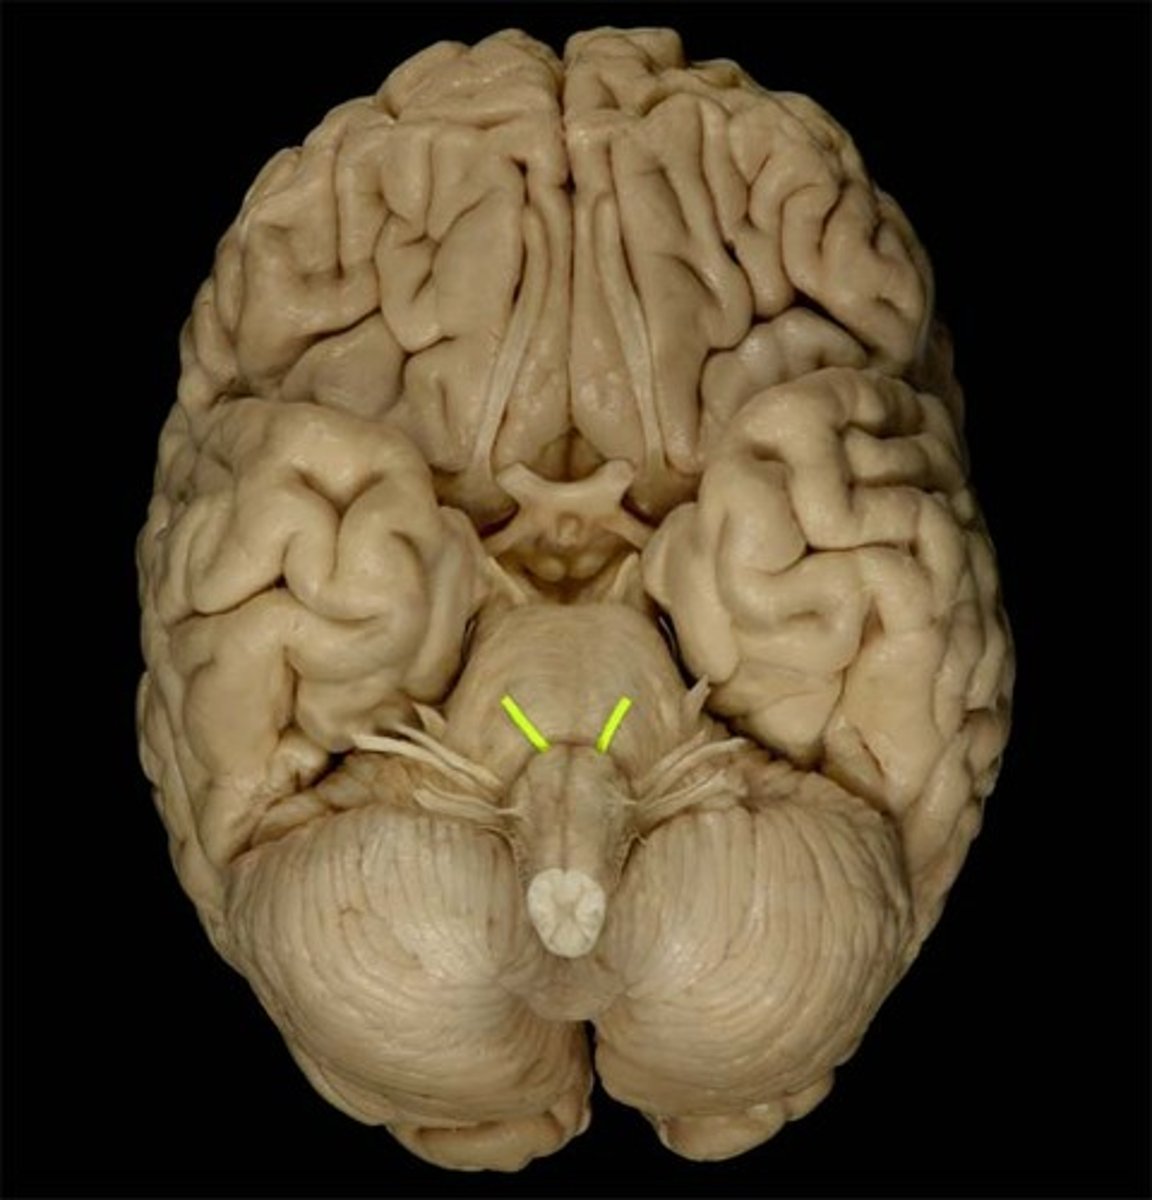

CNIV

trochlear nerve: movement of the eyes, motor, emerge on the brainstem’s dorsal aspect. They travel around the sides of the midbrain and pons to innervate the superior oblique. exit at the superior orbital fissure.

Trochlear nerve

innervates superior oblique muscle (Depresses eye and turns it laterally)